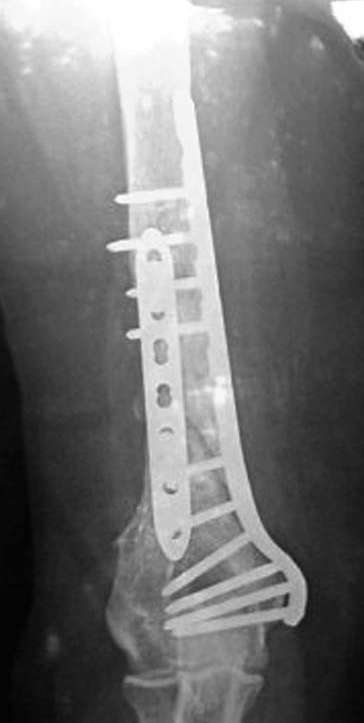

Anatoly F. Lazarev 23 Февраль 2008, 01:04

Типичная положительная ситуация для интрамедуллярного остеосинтеза с

использованием опорного металлокаркаса для компенсации дефекта.

Послеоперационное ведение активное или агрессивно-активное. Каркасы

можно заказать в МАТИ.

Рентгеновская версия реконструкции. хронология:

после операции, 2 мес. после операции, через 1 год

Движения в полном объеме восстановлены к 2 мес. после операции. Если надо могу показать мультик. Сейчас уже прошло более 3 лет, больная не

показывается. Успехов ЛАФ.